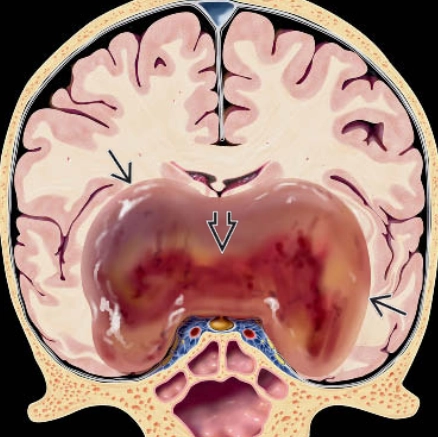

U tế bào thần kinh đệm lan tỏa đường giữa, biến đổi H3 K27 (Diffuse midline glioma, H3 K27-altered)